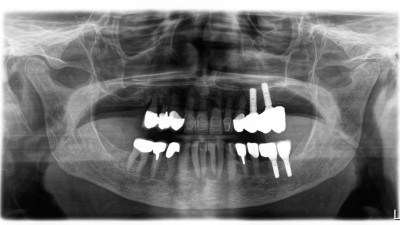

Implantologische Versorgung des kompromittierten Ober- und Unterkiefers im digitalen Workflow (Link öffnet in neuem Fenster)

Die Rehabilitation von Ober- und Unterkiefer mithilfe von Implantaten stellt bei geringem Knochenangebot und insuffizienter Erstversorgung eine hohe Anforderung dar. Digitale Abformungen bei komplexen implantologischen Rekonstruktionen im zahnlosen Kiefer sind vielversprechend und erleichtern sowohl dem Behandler als auch dem Patienten die einzelnen Behandlungssitzungen.

Sofortversorgung mit verschweißtem Metallgerüst - Abbildung 13/© Johannes Petschelt, Sofortimplantation mit Sofortbelastung - Abbildung 1/© Rudolf Kraus, Digitales Ergebnisbild eines präoperativen Scans Unterkiefer: Zahnloser Kieferkamm. Von links nach rechts sind die Positionen 46, 44, 33, 36 markiert/© F. Stelzle | ZI Zahnärztliche Implantologie (2)·2:92-96, Inseriertes Implantat regio 36 nach Entfernung der Osteosyntheseschrauben. Im Kieferkamm ist ein Knochenblocktransplantat sichtbar/© M. Masthoff | ZI Zahnärztliche Implantologie (2)·2:80-84, Bild einer dreidimensionalen digitaler Volumentomographie: Kiefer und Zähne sind zu sehen. Im Unterkiefer fehlen Zähne 33-44./© Universitätsmedizin Mainz, Bild intraoral eines Oberkiefers mit Scanbodies/© Inga Boehncke | ZI Zahnärztliche Implantologie (2)·1:34-40, Ausgangssituation: Zahn 41 mit Komposit-Eckenaufbau/© D. Butzmann | ZI Zahnärztliche Implantologie (1)·4:224-227, Einzelröntgenaufnahme: regio 36 und 37 wurden 2 Straumann-Implantate RN 4,1 mit der Länge 10 mm gesetzt/© Frank Sahm | ZI Zahnärztliche Implantologie (1)·4:212-213, Eingesetztes Individuelles Healing Abutment und Weichgewebsstabilisierung. Das Abutment dichtet die Alveole vollständig ab./© N. Erhard, T. Erhard-Sosna, R. Sader, J. Lorenz | ZI Zahnärztliche Implantologie (1)·4:214-223, Während die Quadrantenstütze des Vertikalextraktorsystems auf den Zähnen 12, 13, 22 und 23 aufliegt, wird Zahn 21 mit einer Seilwinde nach dem Flaschenzugprinzip herausgezogen/© S. Kistler | ZI Zahnärztliche Implantologie (1)·4:228-237, Klinischer Befund: prothetische Versorgung Regio 14, 13, 23, 24 und 34, 33, 43, 44, 28 Jahre post operation/© A. Koch, A. Nitsch, F. Danneil | ZI Zahnärztliche Implantologie (1)·2:90-92, Postoperative 3D-Rekonstruktion der Digitalen Volumentomographie. Zu erkennen sind das patientenspezifische Implantat (PSI) und seine Verankerung am Jochbeinkörper sowie der paranasalen und anterioren Maxilla/© F.S. Siegberg, P. W. Kämmerer, B. Al-Nawas, D. G. E. Thiem | ZI Zahnärztliche Implantologie (1)·2:84-88, Oberkiefer: Hart und Weichgewebsdefizit. Zusätzlicher tiefer knöcherner Defekt von 5 mm mesial des Zahns 22/© A. Rudolph | ZI Zahnärztliche Implantologie (1)·2:108-111, Zahnersatz in situ vor abschließender Unterfütterung mit Randerweiterung/© J. Behring | ZI Zahnärztliche Implantologie (1)·2:100-106, Frakturierter Zahn 34 in situ/© J. Behring | ZI Zahnärztliche Implantologie (1)·1:40-43, Front in Okklusion/© S. Egger, M. Greven, Ch. Berg | ZI Zahnärztliche Implantologie (1)·1:20-27, Fallbericht - Verspäteter Lückenschluss - Abb1/© R. Kraus | ZI-Zahnärztliche Implantologie (1) : S.38-42, Wahl des Analgetikums in der Zahnmedizin/© Heimes D, Kämmerer PW (2023) Analgetika in der Zahnmedizin. wissen kompakt. DOI 10.1007/s11838-023-00174-y / Springer Medizin, Antibiotika in Therapie und Praxis/© J. Heider, B. Al-Nawas (2023) Antibiotika - Update. wissen kompakt. DOI 10.1007/s11838-023-00177-9 / Springer Medizin, One Minute Wonder: Intraligamentäre Anästhesie/© Springer Medizin Verlag GmbH, One Minute Wonder: Spenderknochen für die Kieferregeneration, One Minute Wonder: Subperiostale Implantate/© A.-K.Bär, Ph. Becker | ZI Zahnärztliche Implantologie (1)·4:239, One Minute Wonder: Vitamin-D-Essentials: Das Wichtigste im Überblick, One Minute Wonder: Weichgewebsverdickung an Implantaten, One Minute Wonder: Xenogenes Knochenersatzmaterial bei der Alveolarkammaugmentation/© Ph. Becker, A. Pabst, A.-K.Bär | ZI Zahnärztliche Implantologie (1)·4:211